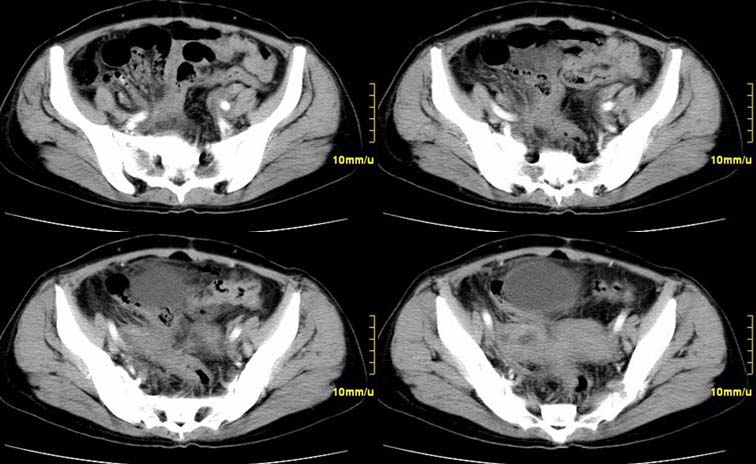

患者,52,右下腹疼痛一月,当时有发热,抗炎治疗20余天,至今仍疼痛,且有低热。

临床特点:

右下腹疼痛一月,当时有发热,抗炎治疗20余天,至今仍疼痛,且有低热,具有典型炎症的临床表现。

ct表现:

右侧附件见一肿块,边缘与周围组织分界不清,增强扫描见肿块明显强化,越到后期强化越明显,中央见坏死,内壁光整,与临近子宫壁、直肠及膀胱后壁均见炎症波及。这种厚壁肿块、内缘光整外缘模糊、增强扫描强化越后越强是附件脓肿典型的ct表现。

诊断:

右侧卵巢输卵管慢性脓肿,炎症波及临近子宫、直肠及膀胱形成粘连。